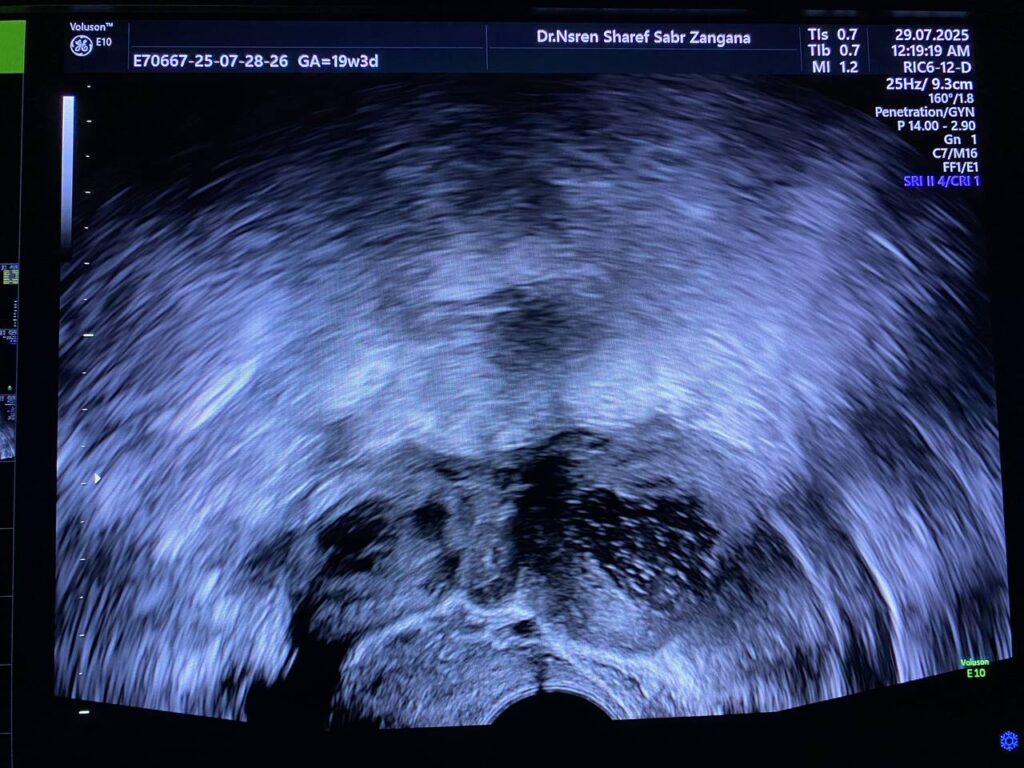

Both ovaries are enlarged in sizes, with increase stromal echogenicity, multiple small follicles > 25 in number, in each ovary, their sizes less than 5mm, with presence of single corpus luteum in the right ovary, its size 15mm, in favors of polycystic like ovaries, should be correlated with clinical picture & hormonal assay

No adnexal mass

Small amount of free pelvic fluid seen, ovulation??